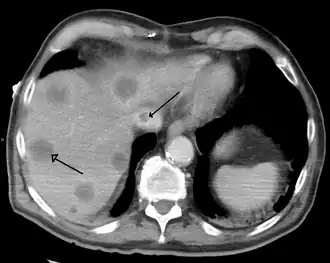

- Primary liver cancer most commonly manifests as hepatocellular carcinoma or cholangiocarcinoma; rarer forms include angiosarcoma and hemangiosarcoma of the liver. (Many liver malignancies are secondary lesions that have metastasized from primary cancers in the gastrointestinal tract and other organs, such as the kidneys, lungs.)[16]

- Budd–Chiari syndrome is the clinical picture caused by occlusion of the hepatic vein.[19]

Imaging tests such as transient elastography, ultrasound and magnetic resonance imaging can be used to show the liver tissue and the bile ducts. Liver biopsy can be performed to examine liver tissue to distinguish between various conditions; tests such as elastography may reduce the need for biopsy in some situations.[54]